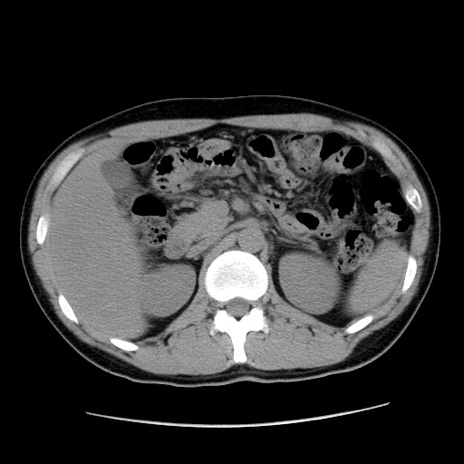

症例36(横断像)

【症例】20歳代 男性

【主訴】心窩部痛

【現病歴】今朝より上腹部痛あり。一旦軽快していたが再度出現したため救急要請。昨日夕に白身の魚を含む刺身を食べた。

【身体所見】BP 136/89mmHg、HR 74/min、BT 37.0℃、腹部:膨満、軟、心窩部に圧痛あり。反跳痛なし、筋性防御なし、腸雑音やや亢進あり。

【データ】WBC 17700、CRP 0.48